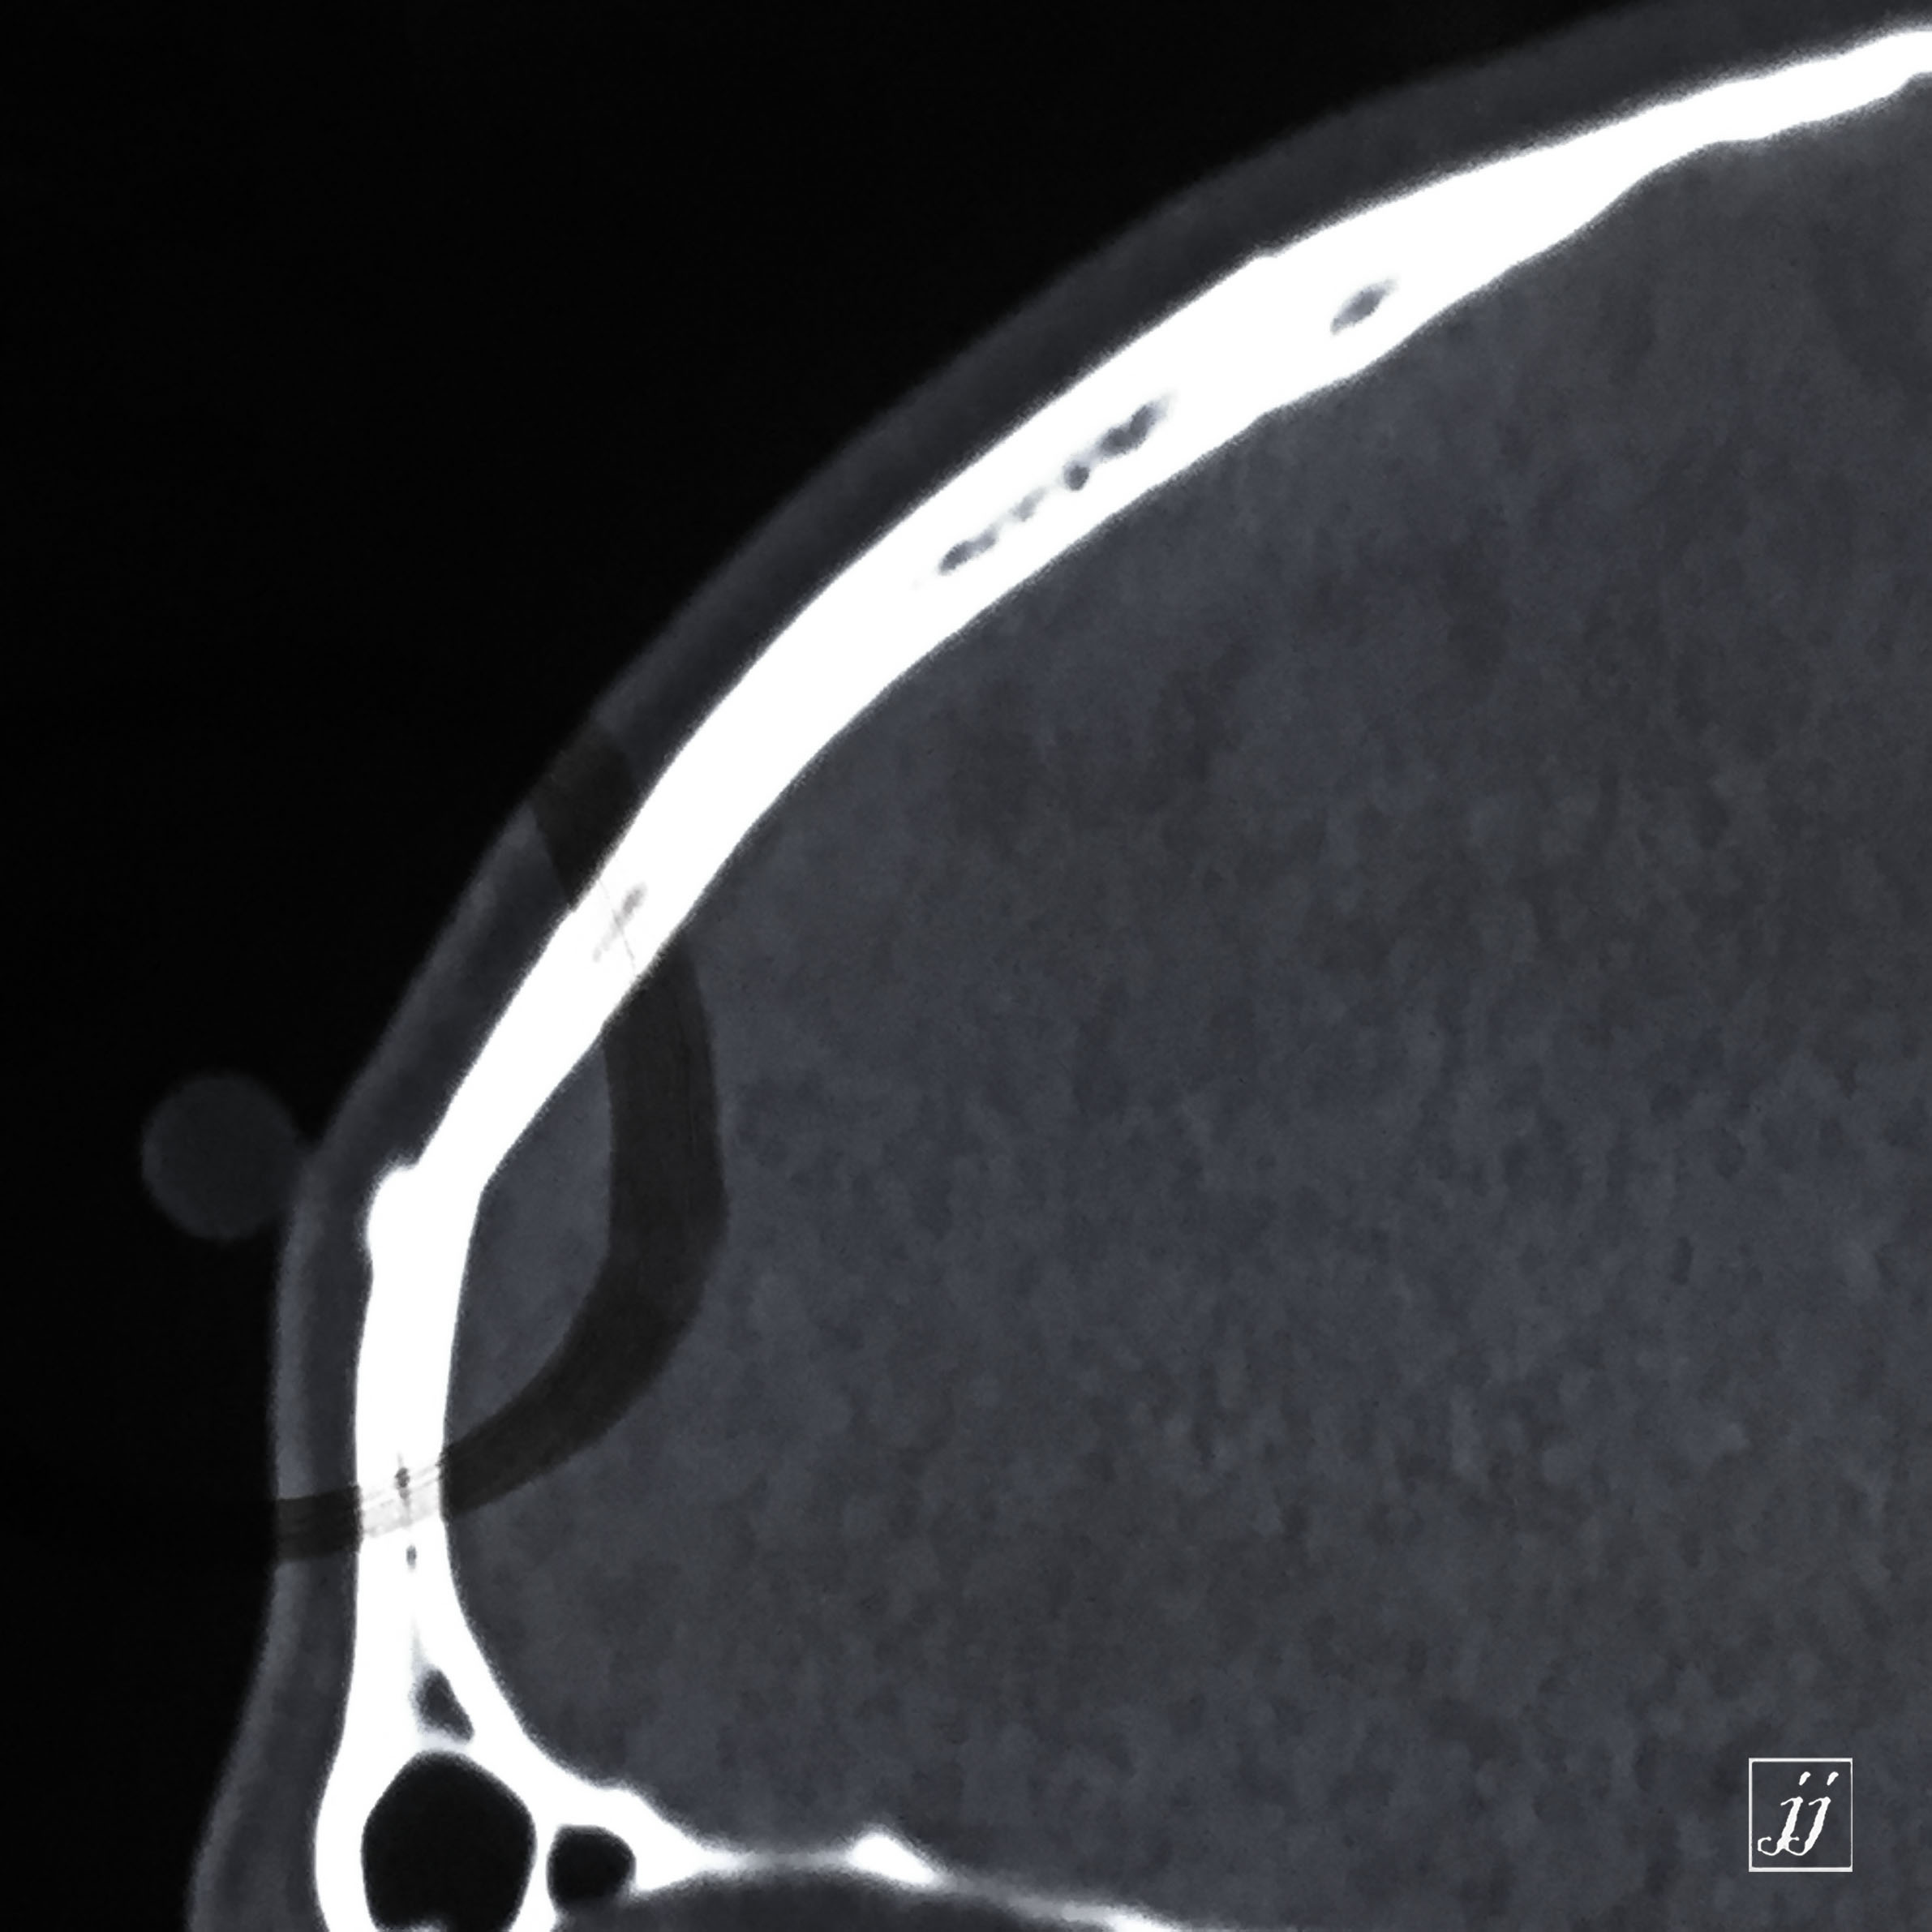

Brain- small osteoma (8)